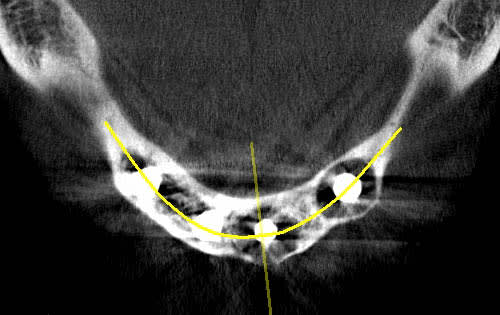

Tu veux dire que désormais, avec la perte de deux implants contigus avulsés pour cause de péri-implantite, le all on four est transformé en all on two?

il faut quand même comprendre pourquoi les 2 implants ont foiré (a mon avis echauffement de l'os qui semble très dens sur le site ) ... sinon les 2 autres auraient foiré aussi

82 ans

pose des implants par un praticien de Metz il y a10 ans. aucun problème particulier.

la patiente est venue me consulter car elle souhaité la même chose au maxillaire. c'est là que j'ai découvert le pot aux roses il y a 3-4 semaines.

je lui ai dit que pour moi il était urgent de virer les implants et de prévoir une reconstitution osseuse au plus vite.

intervention pour retirer le kyste et curetage avec reconstruction osseuse par ROG ( bioos, membrane et tutti quanti..)

empreinte des piliers multi unit après avoir galéré pour retirer les vis cassées (d'où le coût plus élevé que si ça avait été fait avant)

repositionnement de la prothèse sur le modèle en plâtre pour retrouver la DV

réalisation d'un autre complet haut et bas avec DV et courbe occlusale convenable.

la suite dans quelques mois quand il y aura de l'os...

petite précision, je mets des locators, c'est pas l'idéal, mais c'est mieux que rien.

plus tard , je pense ajouter 3 implants.

On peut remarquer la tres jolie expansion realisee par les kystes, certes en 10 ans mais tout en souplesse!